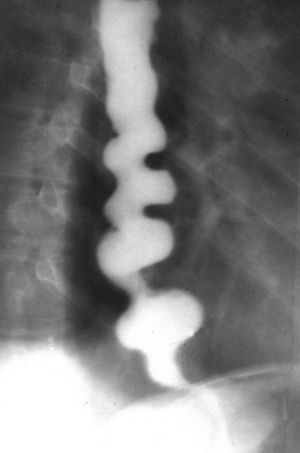

What's your dx??

oesophagospasmus diffusus

Nutcracker esophagus

Diffuse Esophageal Spasm